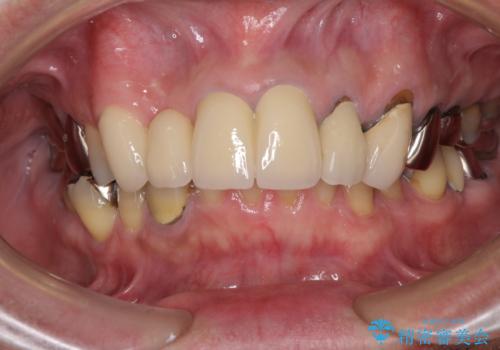

歯肉が少し退縮していたため、補綴治療のやり直しにより歯が少し長く見えるようになりましたが、自然な口元に仕上がり、患者様には大変満足していただきました。

定期的にラグビーをされるとのことなので、マウスピースの装着をかかさないようにお伝えしました。